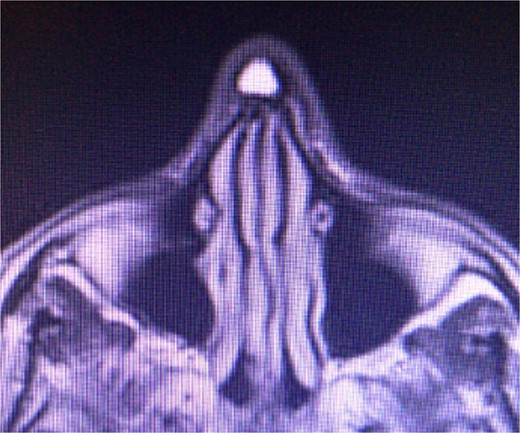

T2-weighted magnetic resonance imaging demonstrating a hyperintense, well defined, 2 × 2 cm lesion in the operative area of the nasal dorsum.